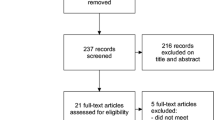

Even though there were no dropouts in the study, the intention-to-treat analysis protocol, established a priori, was followed. The flowchart CONSORT (Consolidated Standards of Reporting Trials) shows the procedures of this study (Fig. 1).